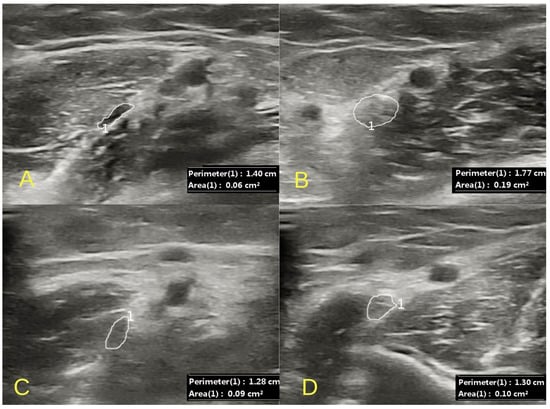

2.1. Clinical Examination and Initial Findings